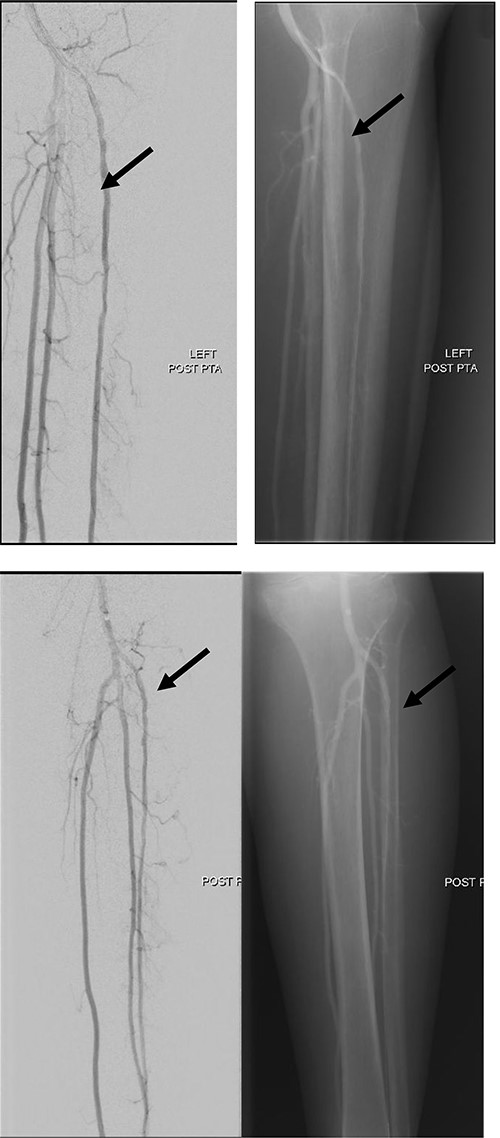

Left lower limb diagnostic angiogram showing occlusion of the ATA with poor flow (arrow).

Angiogram of left distal leg and foot showing poor flow of the distal ATA and dorsalis pedis artery (arrow).